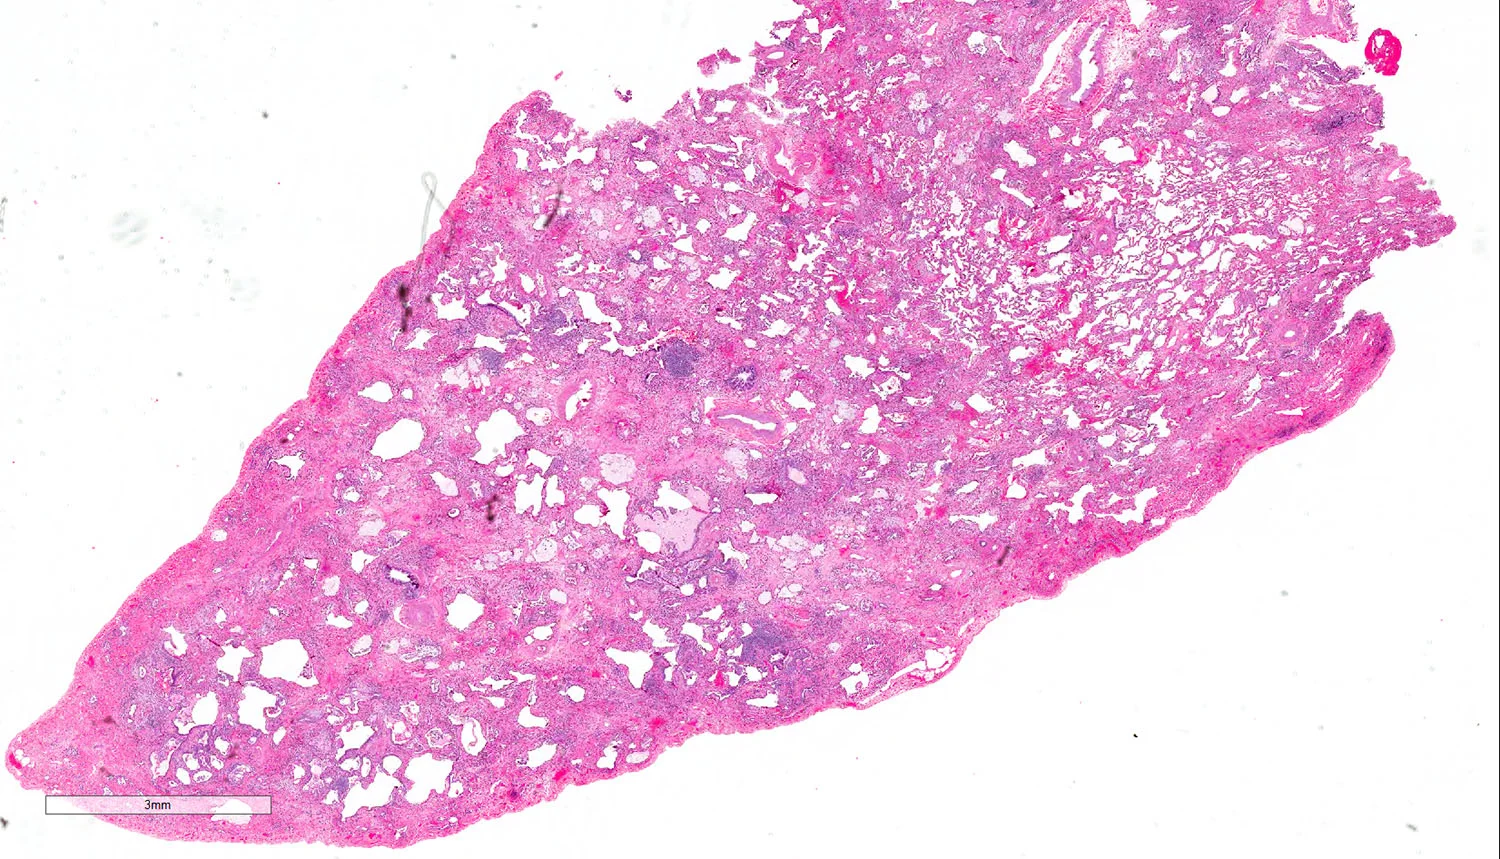

Acute Lung Injury w/ Cellular Interstitial Infiltrates

Acute and organizing diffuse alveolar damage with hyaline membranes (see comment).

Comment: The biopsy shows extensive acute lung injury in the form of hyaline membranes, edema, and areas of organization. This is a nonspecific pattern seen a variety of settings including infection, connective tissues disease, adverse drug reaction, and as an idiopathic entity. Histologic clues to a specific etiology are not identified. No significant background fibrosis to suggest a chronic interstitial lung disease is appreciated. Correlation with final culture studies is suggested to completely exclude infection although there is no necrosis, viral cytopathic effect, granulomas, or extensive neutrophils. Should no definitive etiology be identified, this may represent idiopathic DAD/ARDS.